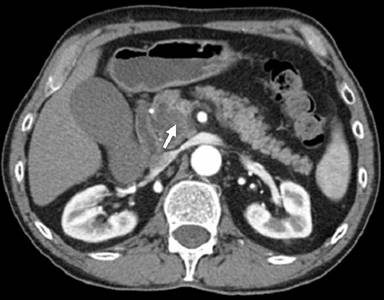

A 66-year-old male was admitted to our hospital suffering from abdominal pain and jaundice. Physical examination was significant for left upper quadrant tenderness. Laboratory examination revealed an elevation of liver function tests and bilirubin levels although serum amylase and lipase, and complete blood count were all within normal range. An abdominal computed tomography scan showed a cystic mass in the head of the pancreas. A horizontal section of a computed tomography scan indicated a cystic mass in the pancreatic uncinate process consisting of a unilocular cystic lesion of 3 cm in diameter and a hyperdense mural nodule of 1.5 cm in diameter (Figure 1). The patient underwent endoscopic retrograde cholangiopancreatography with pancreatic duct brushing, which not revealed a diagnosis of adenocarcinoma. No evidence of distant metastasis was identified. An extended pancreaticoduodenectomy was performed. The operation was uneventful and the patient was discharged from hospital postoperative 12th day. The patient re-admitted to our emergency unit due to upper gastrointestinal bleeding and died postoperative at the 20th day due to sudden gastrointestinal bleeding complication.

Figure 1. Computed tomography scan indicated a cystic mass in the pancreatic uncinate process (arrow). |